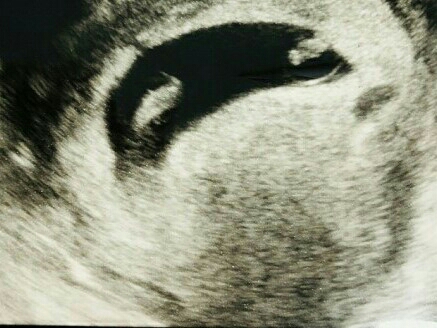

의사 | 일단 초음파부터 볼게요 .

의사 | 자 , 초음파 볼게요 ~ .

의사 | 완전 축복 받으셨는데요? .

의사 | 일란성 쌍둥이에요 -

의사 | 친척들 중 쌍둥이가 있지 않는한 , 쌍둥이는 1% 확률이니까 , 축복이죠 ㅎㅎ .

의사 | 일란성 쌍둥이세요 ㅎㅎ .